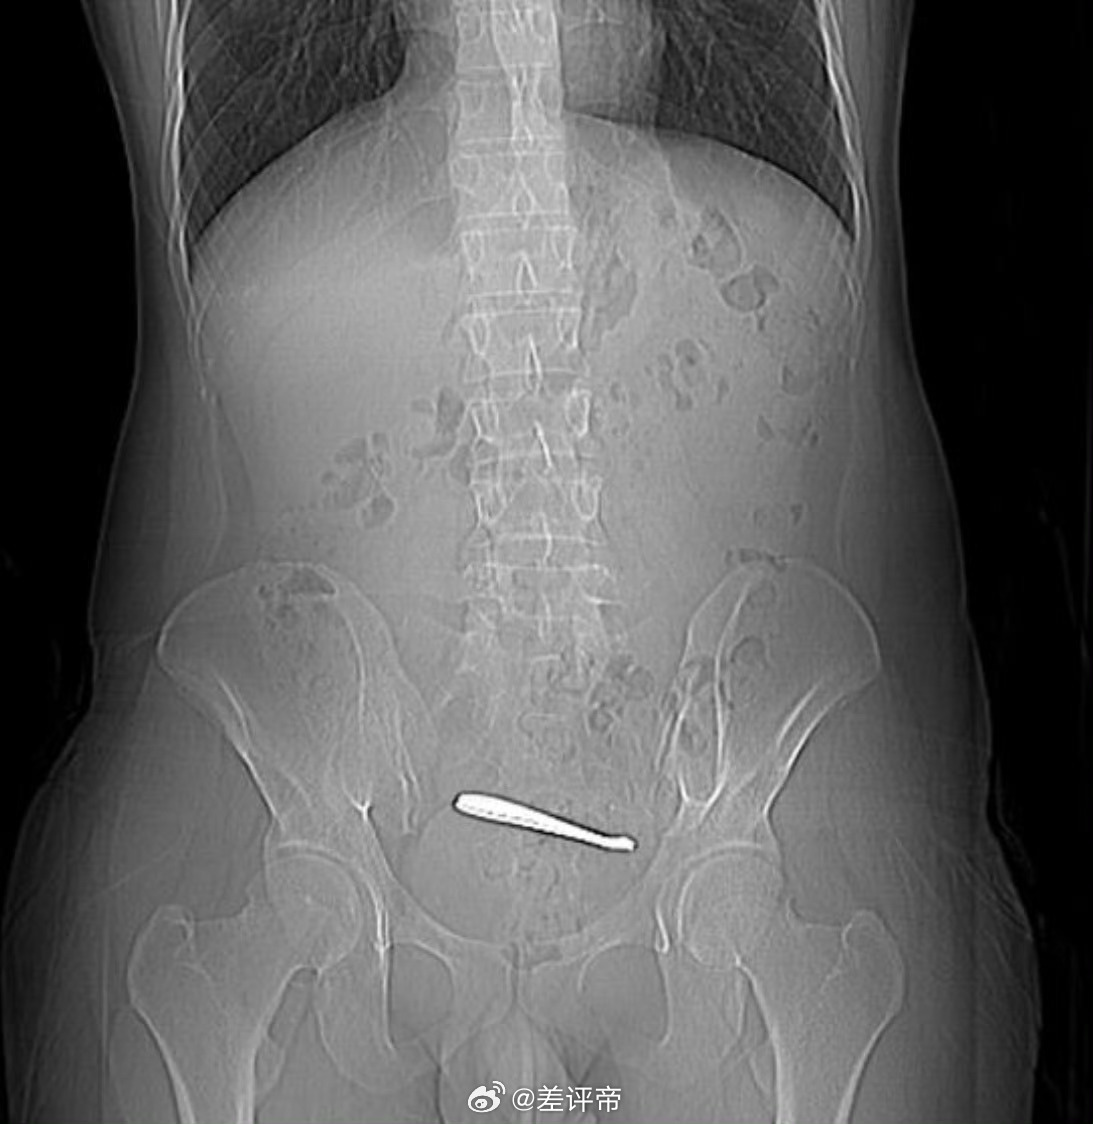

小伙腹痛CT查出肠道卡2把勺子很多人不理解是怎么毫无知觉地吞下两把勺子呢?我假如说这个勺子不是吞的呢是不是就好理解了